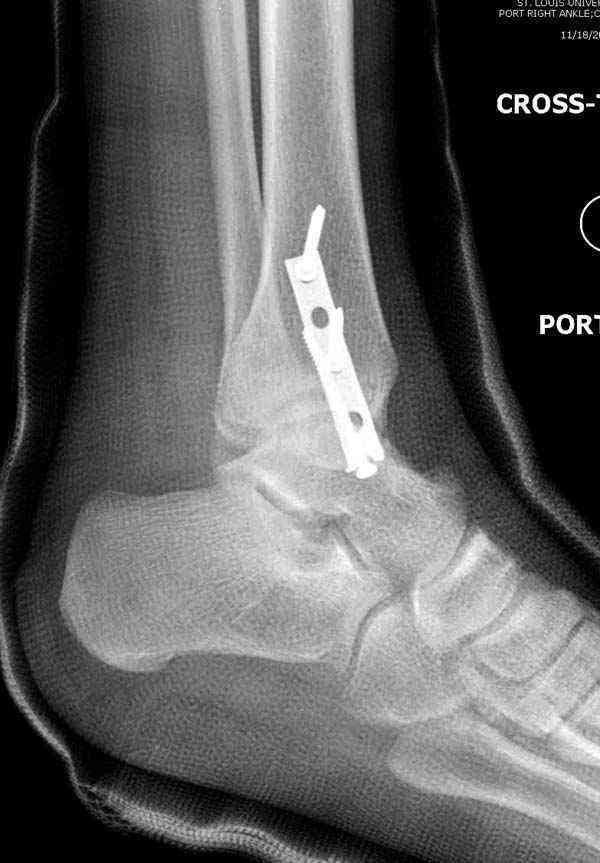

Внутренняя лодыжка

Имя     : 1 Med mal fx Hook plate 0.JPG

Тип     : image/jpeg